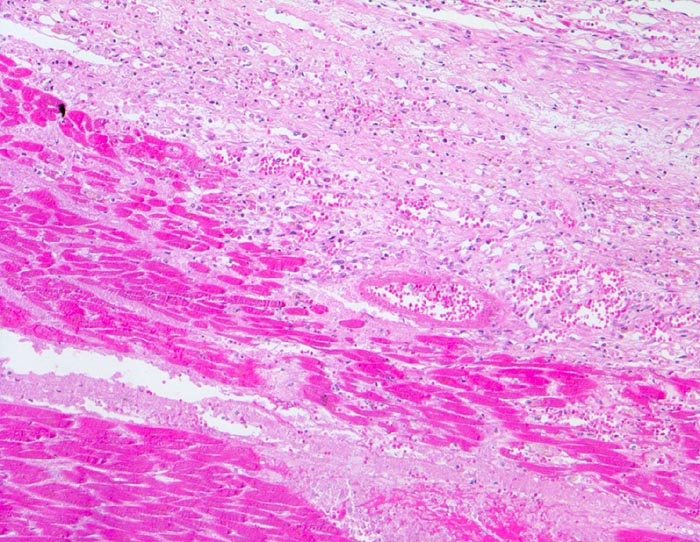

PathoPic – image database / PathoPic ID 4545 - Myokardinfarkt

Myokardinfarkt

Hypereosinophiles Myokard ( Koagulationsnekrose) ohne erkennbare Kernfärbung. Am Rand der Nekrose Granulationsgewebe mit zahlreichen kapillären Gefässen, Makrophagen, bräunliche Siderophagen und Fibroblasten.

Diagnose eines Myokardinfarktes vor 4 Tagen.